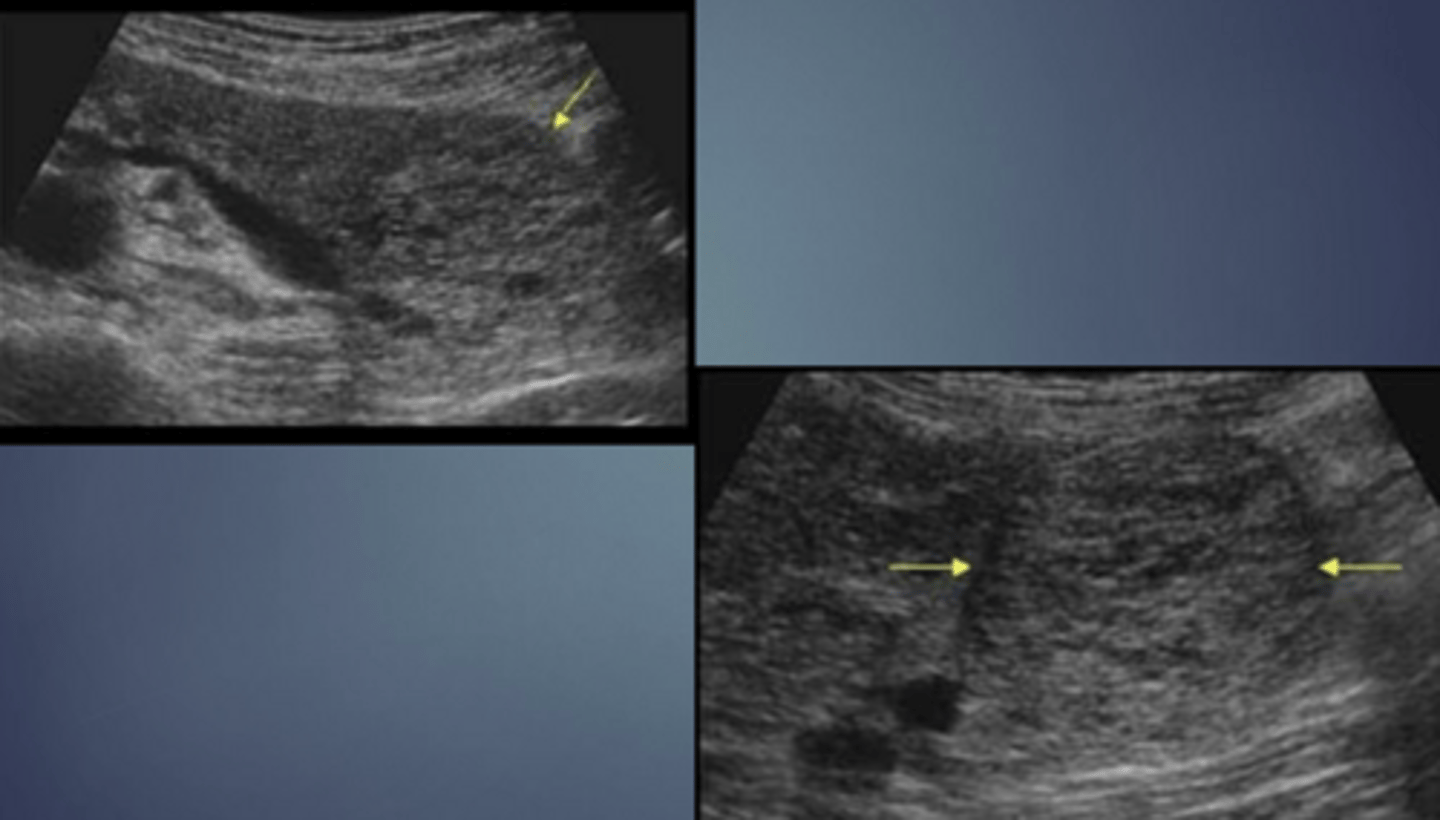

Macrocystic/Mucinous Cystadenoma Sonographic Appearance

-large cyst w/ thick septa

-well circumscribed mass w/ thick/thin walls

-ranges from simple cysts to cysts w/ debris to cysts w/ mural nodules

-cysts w/ an increased # of papillary nodules have a > chance of malignancy

-may contain calcifications

-if mass is large enough it may cayse an obstruction of CBD. pancreatic duct or SPLV

Macrocystic/Mucinous Cystadenoma

Microcystic

Macrocystic

Carcinoma of Pancreas Sonographic Appearance

-80% are focal lesions

-loss of normal pancreatic parenchymal pattern

-irregular, nodular border

-localized change in echo texture

-gland enlarges at mass site

-henerally hypoechoic

-CBD, CHDs and pancreatic ducts may be dilated (courvoisier's)

-normal vascular landmarks may be obliterated or displaced (compressed IVC, spleen enlarged due to cmopression of SPLV)

-metastases to surrounding organs (liver, adrenal, GB, lymph nodes)

-ascites

Carcinoma of Pancreas